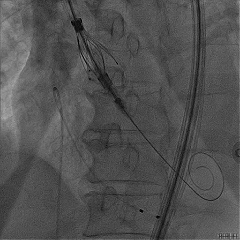

术后右窦中心造影,无漏,无AVB

TEER环节